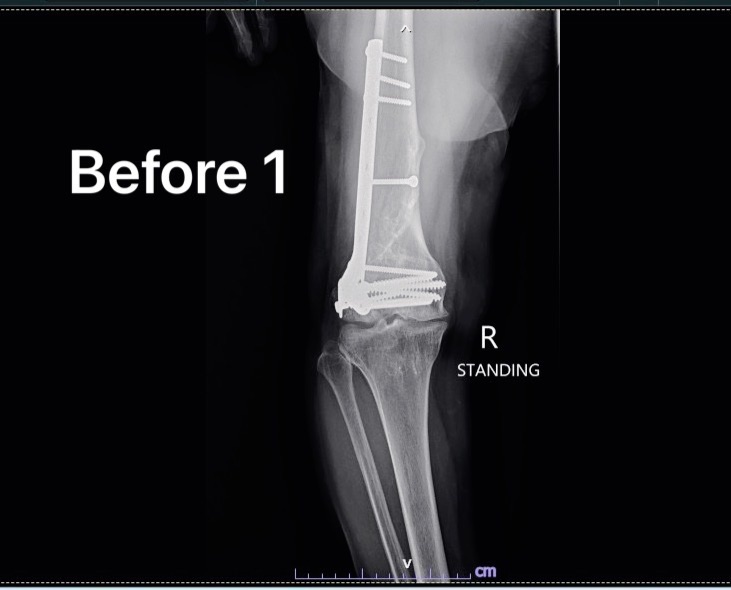

รวมภาพ X-ray Before/After Total Knee